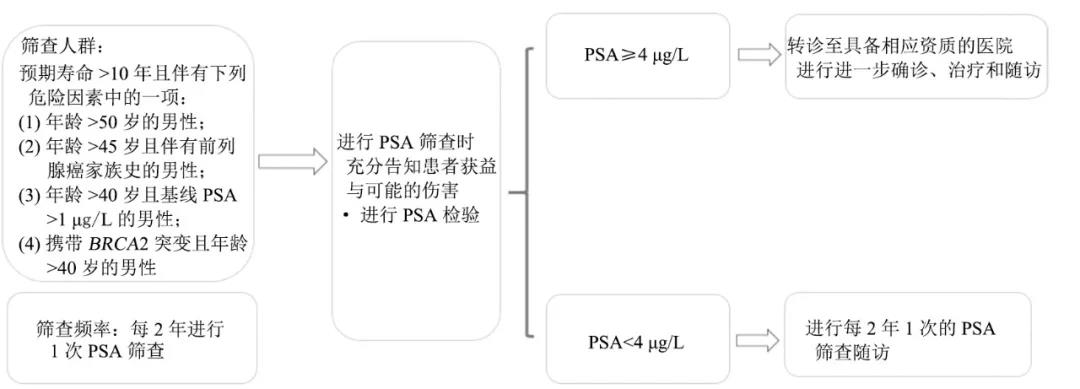

1 前列腺癌流行病学特征随着中国经济水平提高、人民生活水平改善和人均寿命延长,中国前列腺癌的发病率呈显著上升趋势,正逐步成为影响中国中老年男性健康的重要疾病[1]...

首部兼具国际水准和中国特色的前列腺癌诊疗——《CSCO前列腺癌诊疗指南》,近日重磅发布,前列腺癌领域多位专家在线解读了指南相关内容,医脉通整理了指南要点,供读者参...